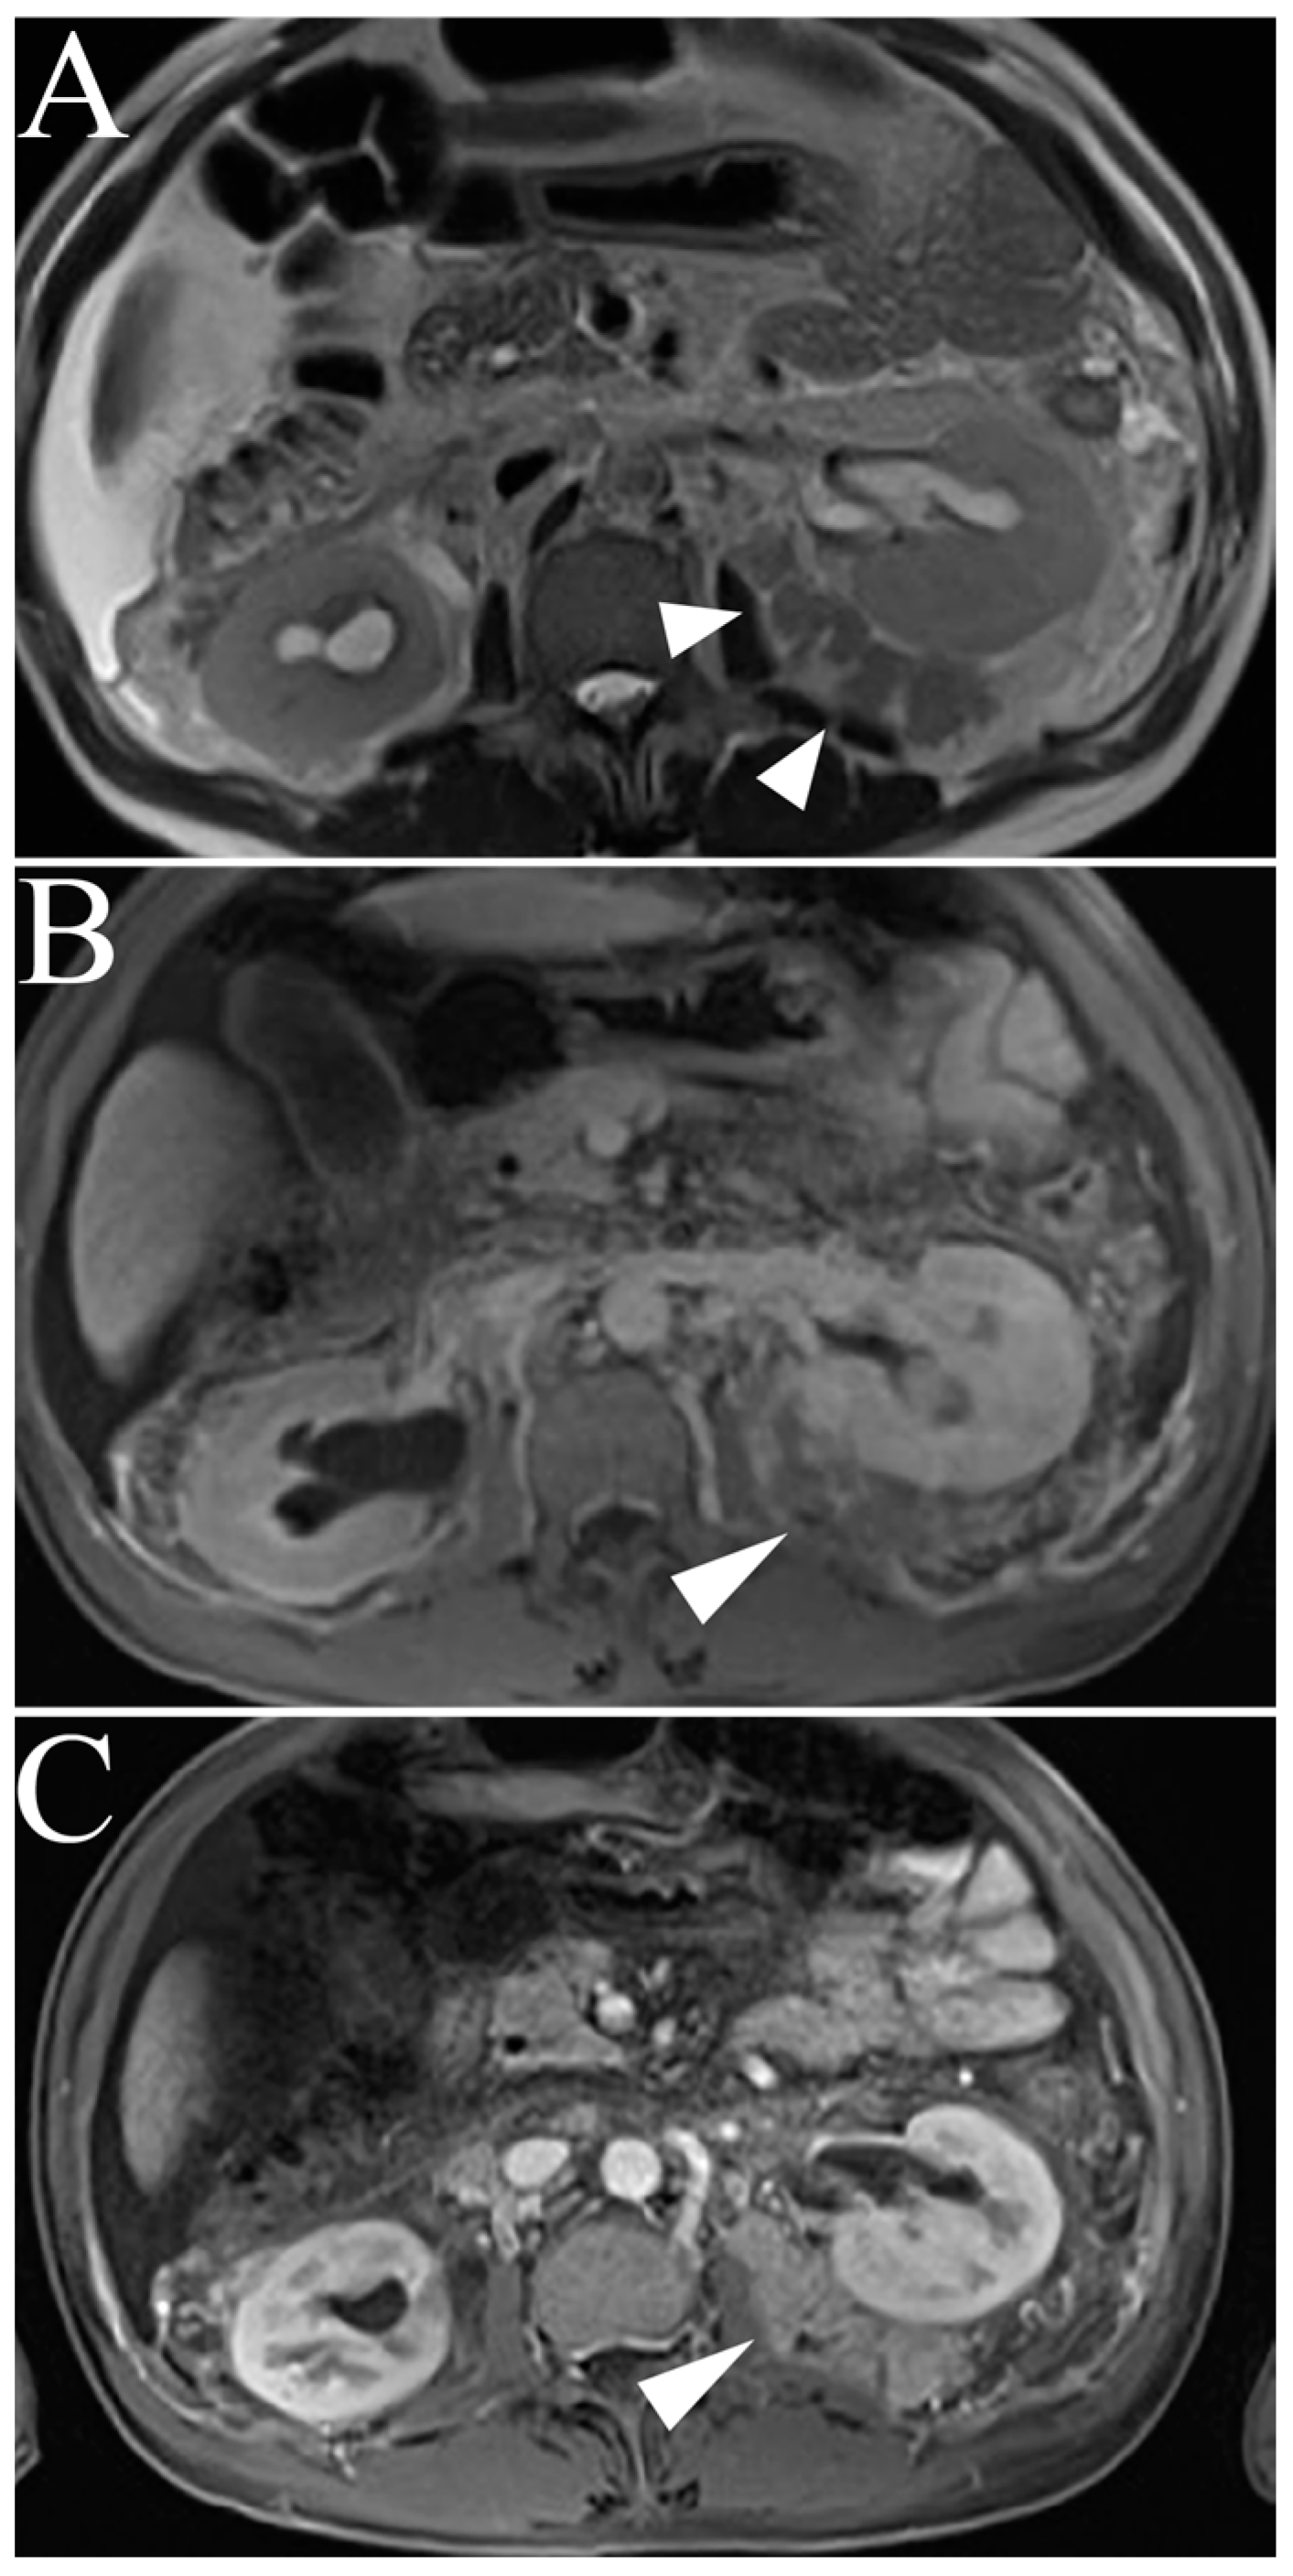

| Type 1 Papillary RCC | T2-hypointense Uniform progressive delayed enhancement Well-circumscribed, homogenous, peripherally-located |

| Type 2 Papillary RCC | Heterogenous T2 signal intensity Heterogenous enhancement Larger with more indistinct margin vs versus Type 1 pRCC |

| Renal Lymphoma | Low to intermediate T1 and T2 signal intensity Mild, delayed, homogenous enhancement Multiple 1–3 cm solitary masses |

| Transitional Cell Carcinoma | Intermediate T1 and T2 signal intensity Delayed, heterogenous enhancement Filling defects and soft masses when urine is present as contrast medium |